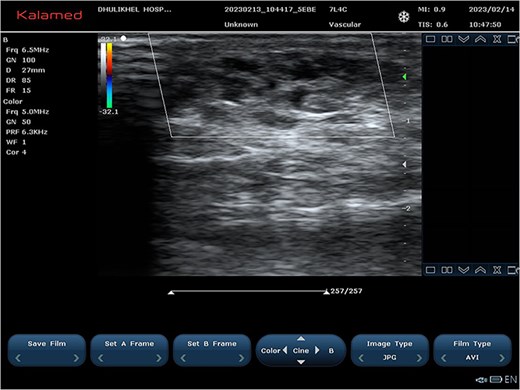

Color and spectral Doppler ultrasonography revealed a multicystic, low-flow vascular lesion (Fig. 2). Based on these findings, a diagnosis of sporadic, unifocal, slow-flow VM was established. Pre-procedure coagulation screening, including prothrombin time, and baseline renal function tests were conducted.

(A and B) Ultrasound images demonstrating cystic vascular spaces with non-pulsatile venous flow.